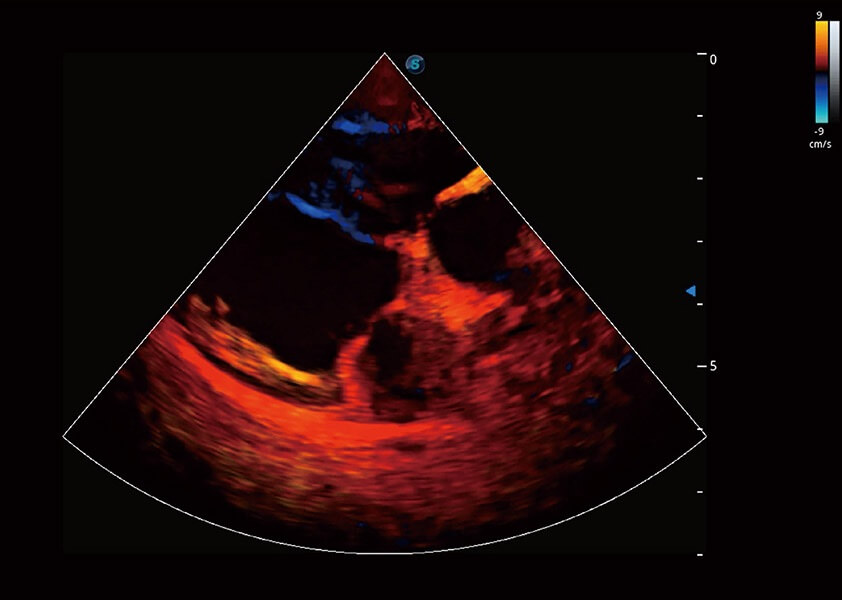

ProPet 60 作为一款高端台式动物超声设备,为动物医生的日常诊断提供了一系列贴合动物临床需求、解决临床实际问题的高级成像功能。凭借全系列高清探头,满足医生对腹部、心脏、生殖、浅表、肌骨等成像的所有需求,切实帮助您提升检查效率,提高诊断信心。

动物是人类最亲密的朋友和最值得信赖的伙伴。米兰官方网站也一直致力于探索动物专用的超声影像解决方案。 全新推出的ProPet系列,是米兰官方网站在动物超声影像智能化、专业化、精准化的一次跨越式革新。动物不能用言语来表述自己的不适,通过超声影像,ProPet系列搭建了动物医生与不同物种沟通的“桥梁”,为动物医生注入了“治愈之力”。